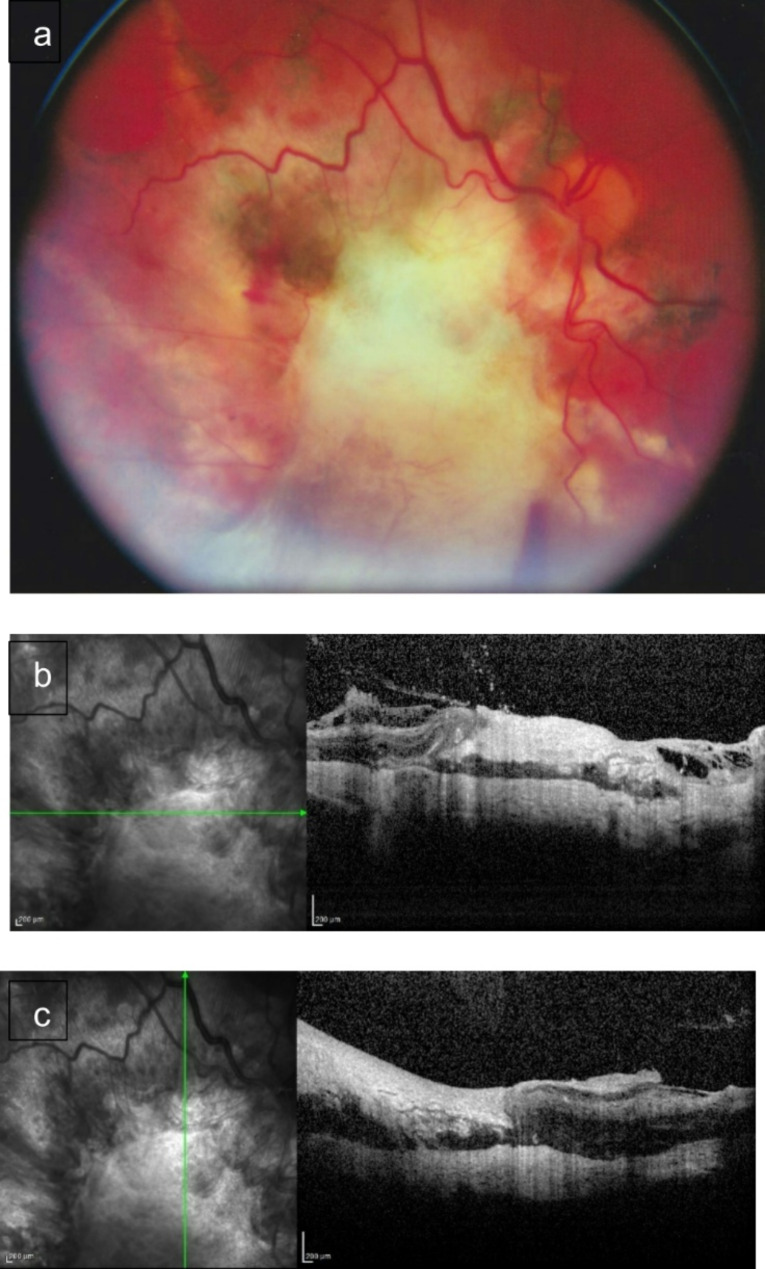

Background: To analyse the anatomical and functional results of pars plana vitrectomy in patients with Chorioretinitis Sclopetaria caused by severe combat-related ocular trauma.

Results: Postoperative best-corrected visual acuity improved in 18 patients (75%) but remained unchanged in 5 patients (20.8%). In 1 patient (4.2%), best-corrected visual acuity deteriorated due to the development of traumatic optic neuropathy. Retinal detachment was noted in 13 patients, whereas a macular hole was present in 5 patients. In 2 patients, both retinal detachment and macular holes were diagnosed simultaneously. After pars plana vitrectomy, retinal reattachment was achieved in 23 patients (95.8%). In one case, reattachment was unsuccessful. The localization of Chorioretinitis Sclopetaria was significantly associated with the final best-corrected visual acuity, with the best surgical outcome observed in patients with Chorioretinitis Sclopetaria located in the inferior sector of the fundus (p < 0.05). The outcome of pars plana vitrectomy for Chorioretinitis Sclopetaria with concomitant retinal detachment is significantly better when the procedure is performed earlier following blast injury.

Conclusions: Chorioretinitis Sclopetaria following blast ocular trauma is characterized by a significant, persistent, best-corrected visual acuity decreasing, a high frequency of vitreous haemorrhages, macular holes, and retinal detachment. Pars plana vitrectomy in Chorioretinitis Sclopetaria has shown considerable effectiveness in improving visual function, retinal reattachment, and macular hole closure in patients with blast-related ocular trauma.